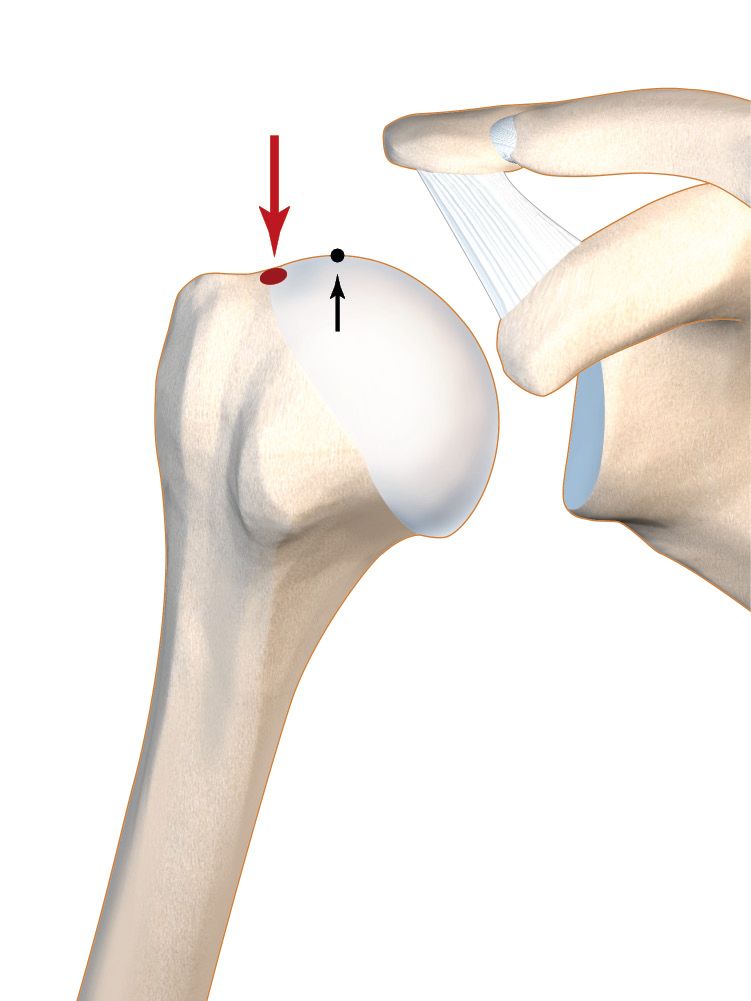

- The mechanical constraints exerted by the reverse implant and the upwards shearing force require a solid primary fixation to allow for early rehabilitation. Solid bone integration seems mainly to occur around the ring. There is poor integration around the fins and post, as we have found for the few cases we have had to remove a stemless implant (Fig. 2).

- Bone stock assessment: bone quality (e.g. necrosis, cysts, sepsis) should be assessed prior to surgery, using sliced images, along with a review of past medical history. However, the majority of the evaluation occurs in theatre during surgery using the thumb press test. This is a new but essential practice and habit: the density of the metaphyseal bone can be estimated by pressing firmly with the thumb. The results will determine the best surgical option.

5. Bone quality assessment and thumb test

a. Essential

b. Not dependent on thumb size and ultimately depends very little on pressure: the bone quality is either good or bad.

c. Adjusting reamer, trial and implant size according to thumb test (Table 3)